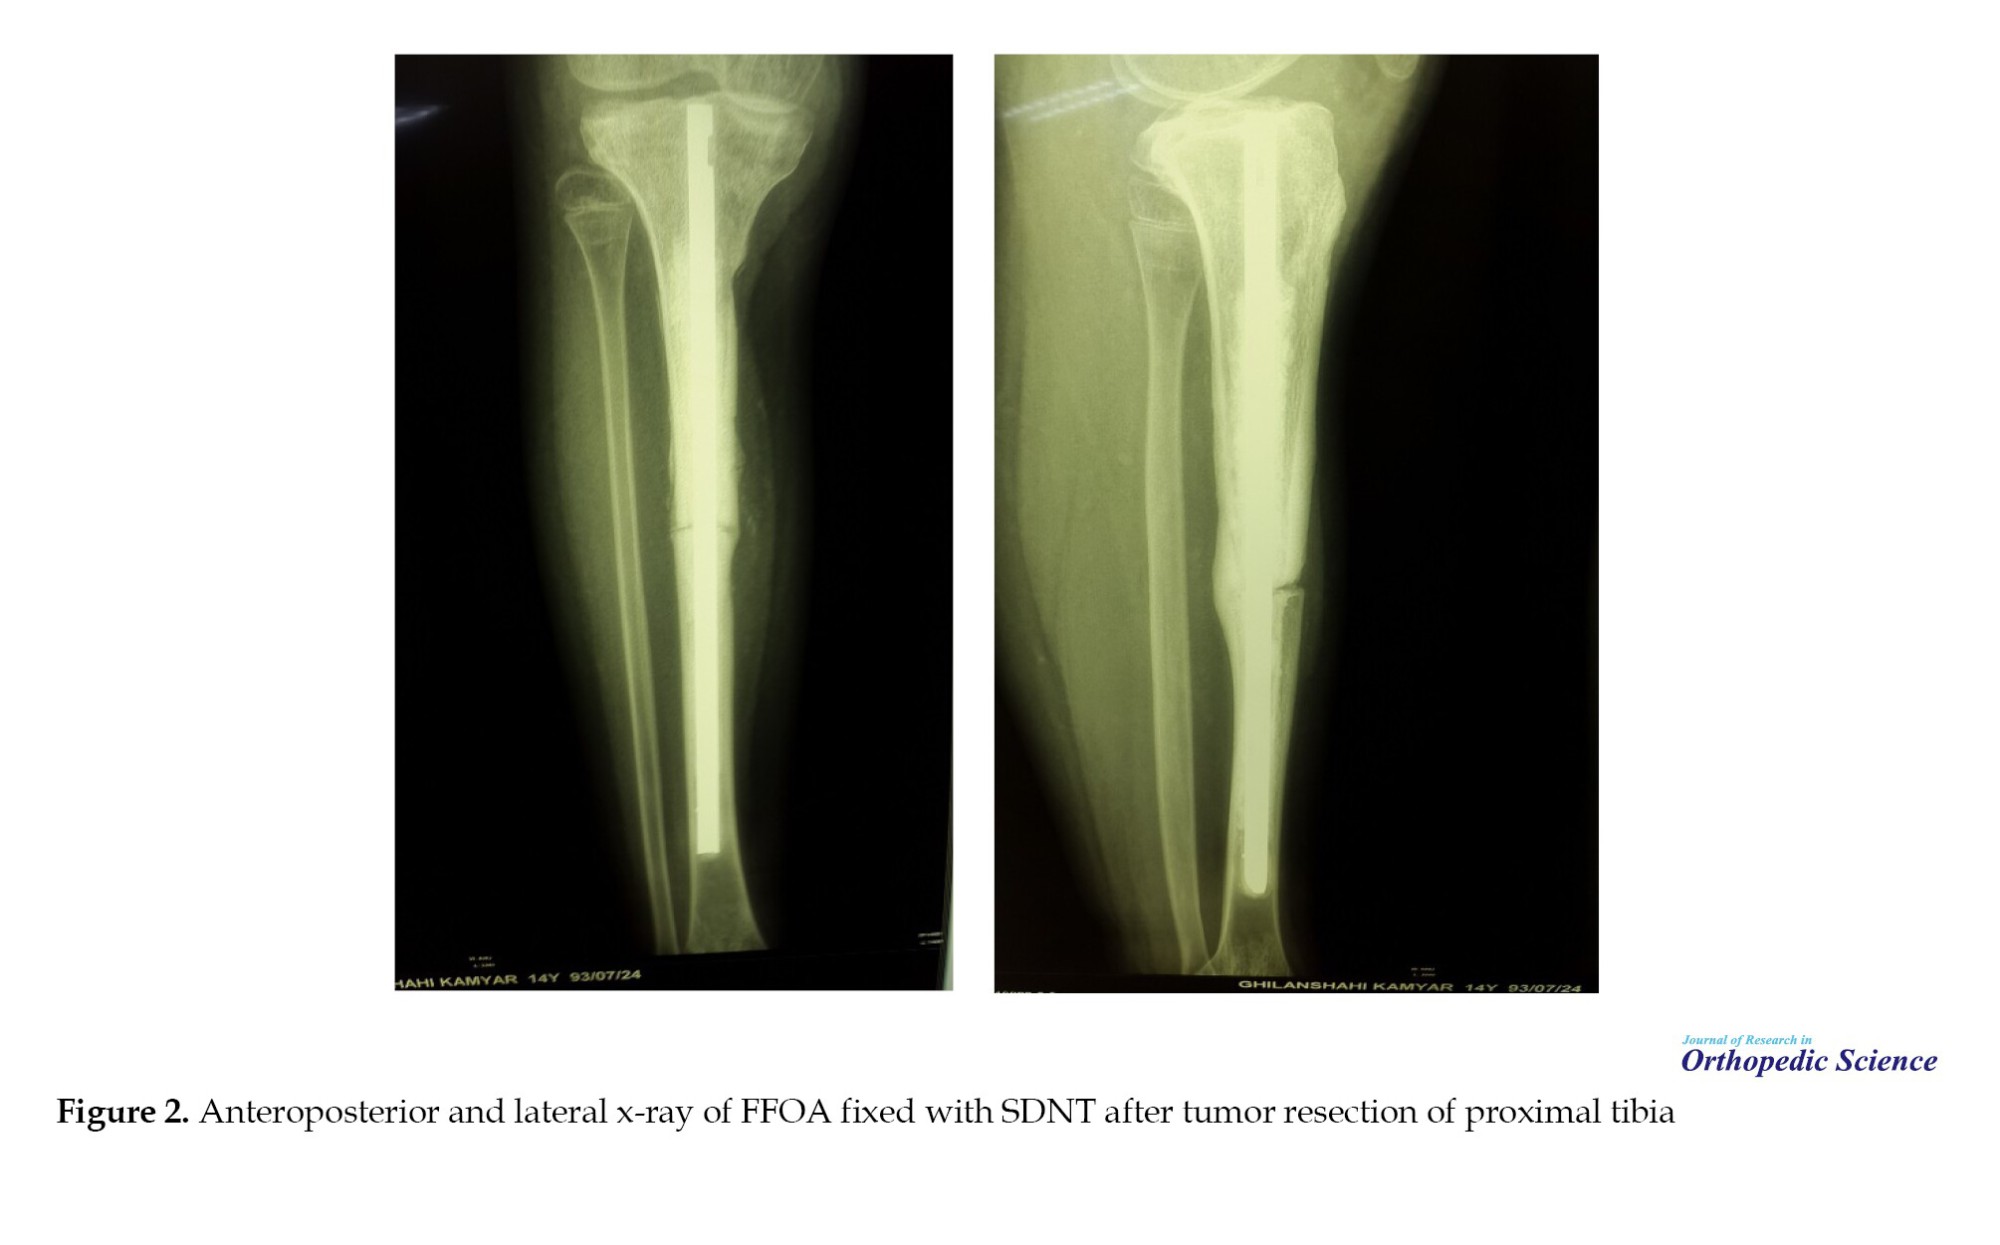

The Mean±SD time to bone :union: was 9.71±3.05 months, with successful allograft-host integration observed radiographically (Figures 1 and 2).

Postoperative complications occurred in 48.88% (n=20) of patients. Delayed :union: was the most common complication (24.39%, n=10), followed by infection (14.64%, n=6), drop foot (4.88%, n=2), nail bending (2.44%, n=1), non:union: (2.44%, n=1), and superficial wound issues (2.44%, n=1) (Table 2). Notably, no allograft fractures occurred, with nail bending being the only mechanical failure observed, as seen in postoperative radiographs of distal femur and proximal tibia reconstructions (Figure 1 for distal femur; Figure 2 for proximal tibia) [1]. Reoperations were required in 48.78% (n=20) of cases, including amputation (14.63%, n=6), bone grafting (7.32%, n=3), irrigation and debridement (9.76%, n=4), knee release (2.44%, n=1), lung surgery (2.44%, n=1), vascular grafting (2.44%, n=1), and prosthesis placement (7.32%, n=3). Intraoperative complications occurred in 12.2% (n=5) of cases.